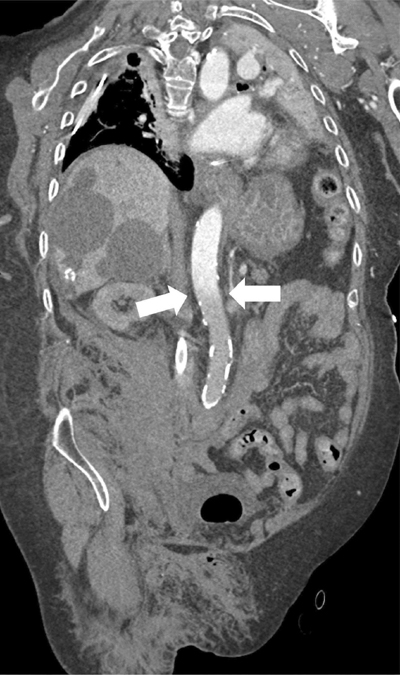

CTA demonstrated good opacification of the thoracic aorta up to the level of the superior mesenteric artery (SMA). However, more distally, no marked enhancement of the aorta and visceral vessels was obtained (Figures 3–5).

Figure 3

Paracoronal reformatted image of the watershed zone (white arrows) at the level of the superior mesenteric artery (SMA).

In this case, no luminal contrast opacification nor active haemorrhage distal to the SMA was present due to the watershed phenomenon, with the blurred area at the level of the SMA and despite the haemorrhage surrounding the right superficial femoral artery.

Since distal to the SMA no vascular enhancement was obtainable, active bleeding could not be ruled out. Awareness of the watershed phenomenon is crucial, since artefacts can be mistaken for pseudolesions such as thrombus, dissection, or vascular occlusion. The watershed area can also potentially obscure true pathology [2], with potentially fatal consequences, as in this case where an active bleeding could be overlooked.